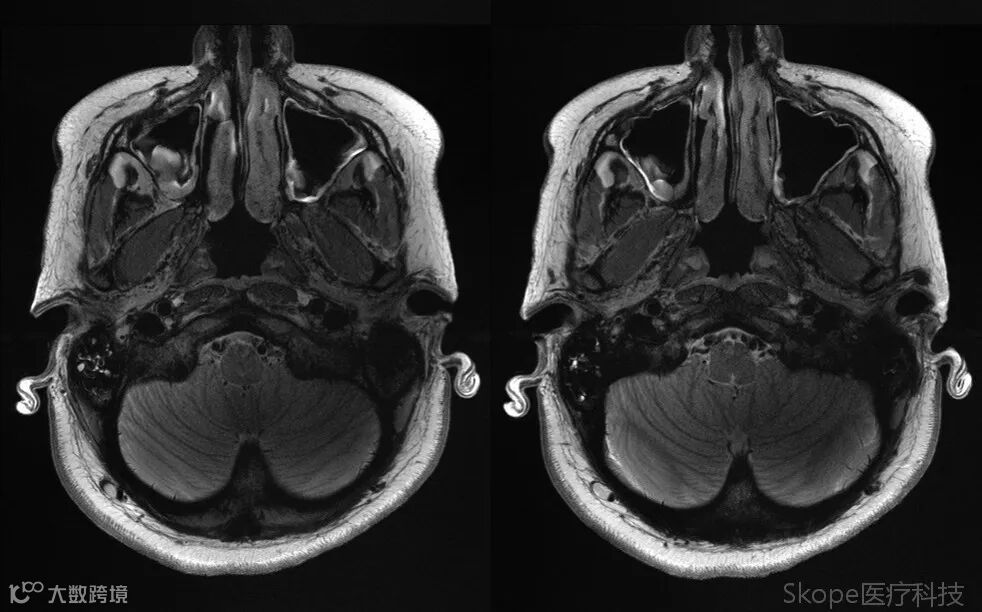

Axial T2 TSE

3D T2 Space FLAIR FS

采用高加速因子的同时,仍保持了高分辨率和高信噪比。